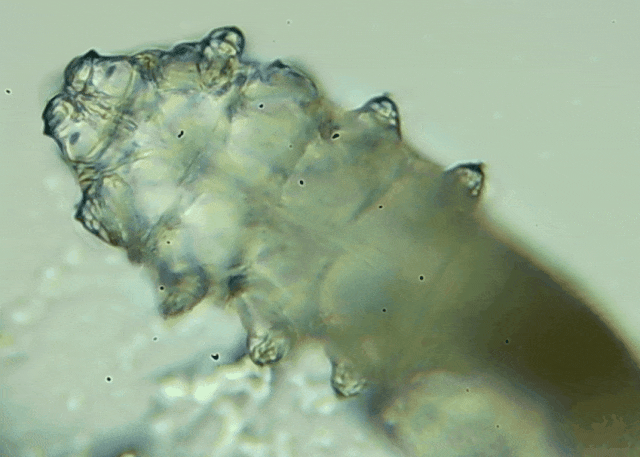

蠕形螨是一類肉眼看不見的寄生螨,常見的有毛囊蠕形螨和皮脂蠕形螨,常駐在人類的毛囊和皮脂腺里,尤其是眼睛的瞼板腺和睫毛根部。數(shù)量少時,蠕形螨能與人體“和平共處”,但一旦你免疫力下降、油脂分泌旺盛或清潔不到位,他們就會以你難以想象的速度瘋狂繁殖。

操作:醫(yī)生會在每只眼睛的上下眼瞼各拔3根典型睫毛,置于光學顯微鏡下觀察。報告解讀:任一眼瞼螨蟲數(shù)量≥3 條 →陽性,需要干預。優(yōu)勢:無創(chuàng)、快速、直觀;當場給你看“活的”螨蟲在睫毛上爬,視覺沖擊堪比大片。